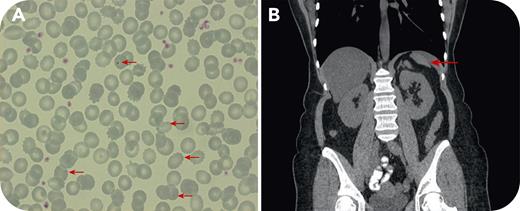

An asymptomatic 55-year-old woman presented with thrombocytosis discovered 2 years earlier. Laboratory testing revealed the following: hemoglobin 13.1 g/dL, red blood cell count 5.04 × 109/L, hematocrit 41.8%, mean corpuscular volume 83 fL, mean corpuscular hemoglobin concentration 31.3 g/dL, leukocytes 10.87 × 109/L (neutrophils 43%, lymphocytes 45%, monocytes 5%, eosinophils 4%), and platelets 513 × 109/L. Serum ferritin levels were low at 8 ng/mL. Physical examination was unremarkable. Serum ferritin normalized with adequate iron replacement, but blood counts, including platelets, remained unchanged. Peripheral blood smear examination confirmed mild thrombocytosis but also revealed Howell-Jolly bodies and target cells (panel A; original magnification ×100, arrows). Testing for JAK2-V617F, CALR9, and c-MPL mutations was negative. There was no history of splenectomy or sickle cell syndrome. In abdominal ultrasonography, the spleen “was not clearly visible.” An abdominal computed tomography (CT) scan revealed an elongated left liver lobe extending to the left hypochondrium and markedly decreased spleen dimensions (panel B, arrow). An extensive retrospective search in the patient’s medical record revealed that splenic hypoplasia was also detected, but not reported, in another CT performed 6 years earlier. There was no history of severe infections. Causes of acquired splenic atrophy/hypoplasia, including splenic vessel thrombosis, coeliac disease, sarcoidosis, and autoimmune disorders, were excluded.

Congenital or acquired splenic hypoplasia without prior splenectomy should be considered as an extremely rare “spot” diagnosis in the differential diagnosis of reactive thrombocytosis, by seeking Howell-Jolly bodies in the patient’s peripheral blood smear.